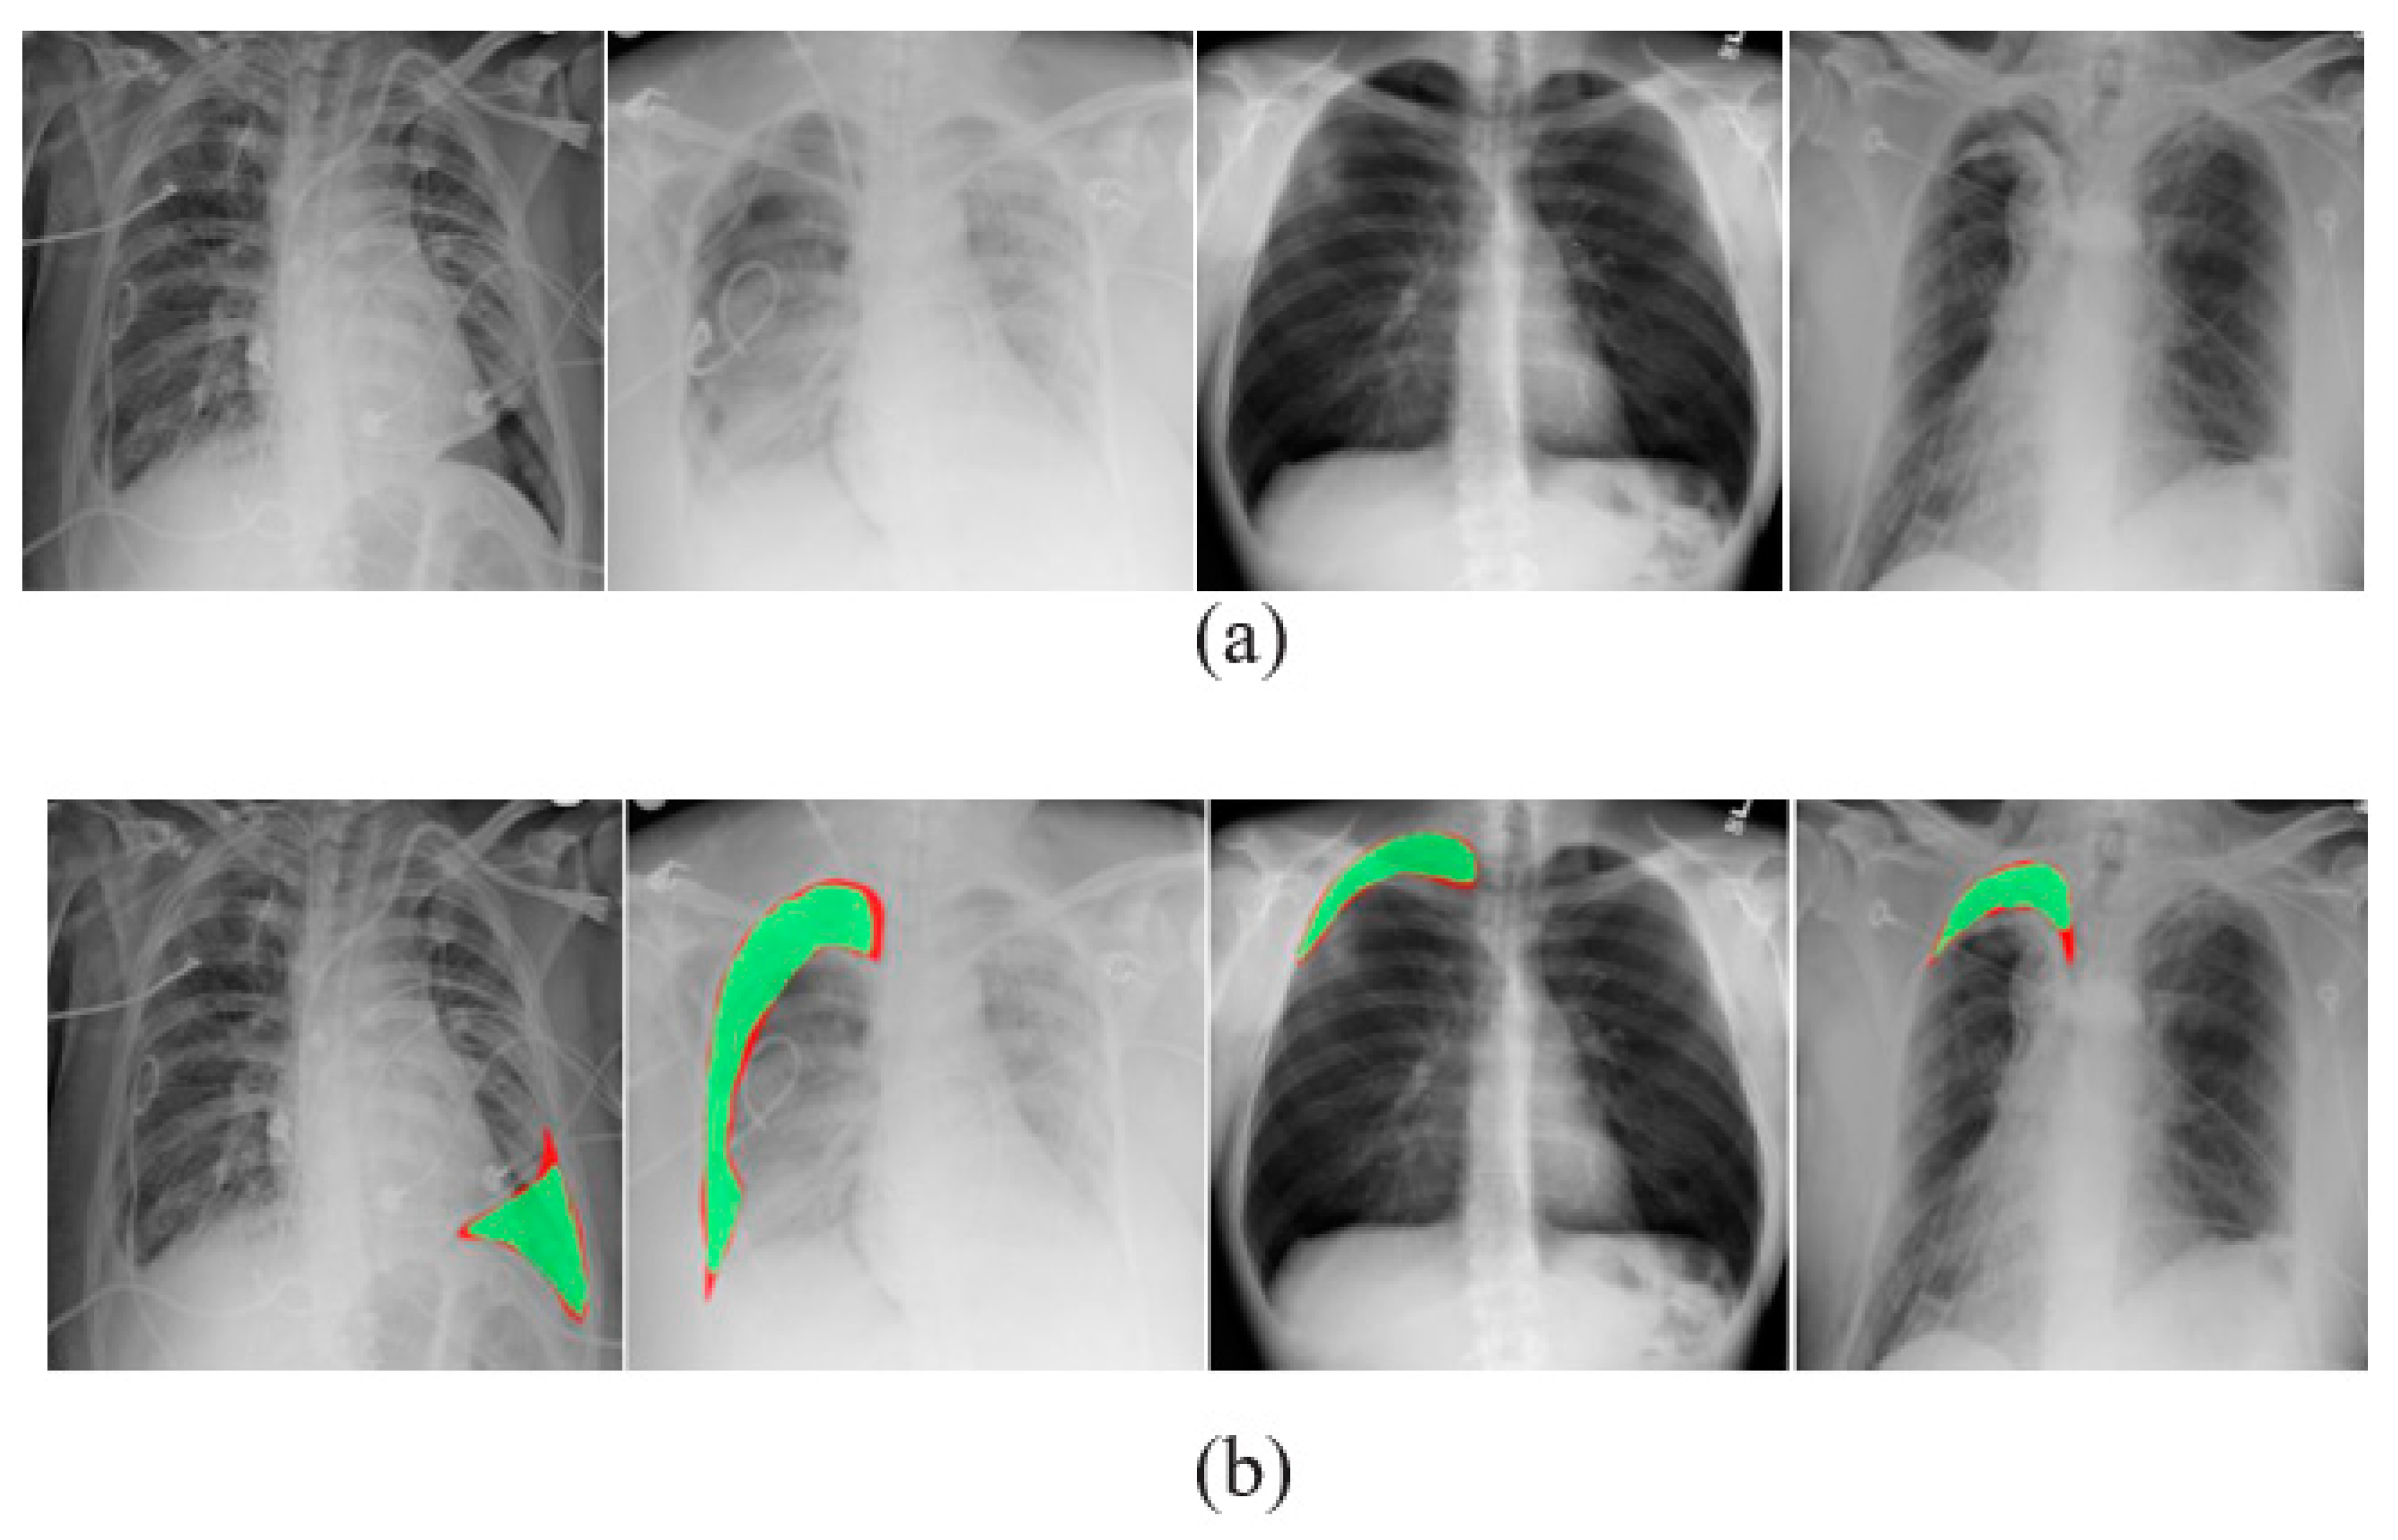

3.4. Image Segmentation